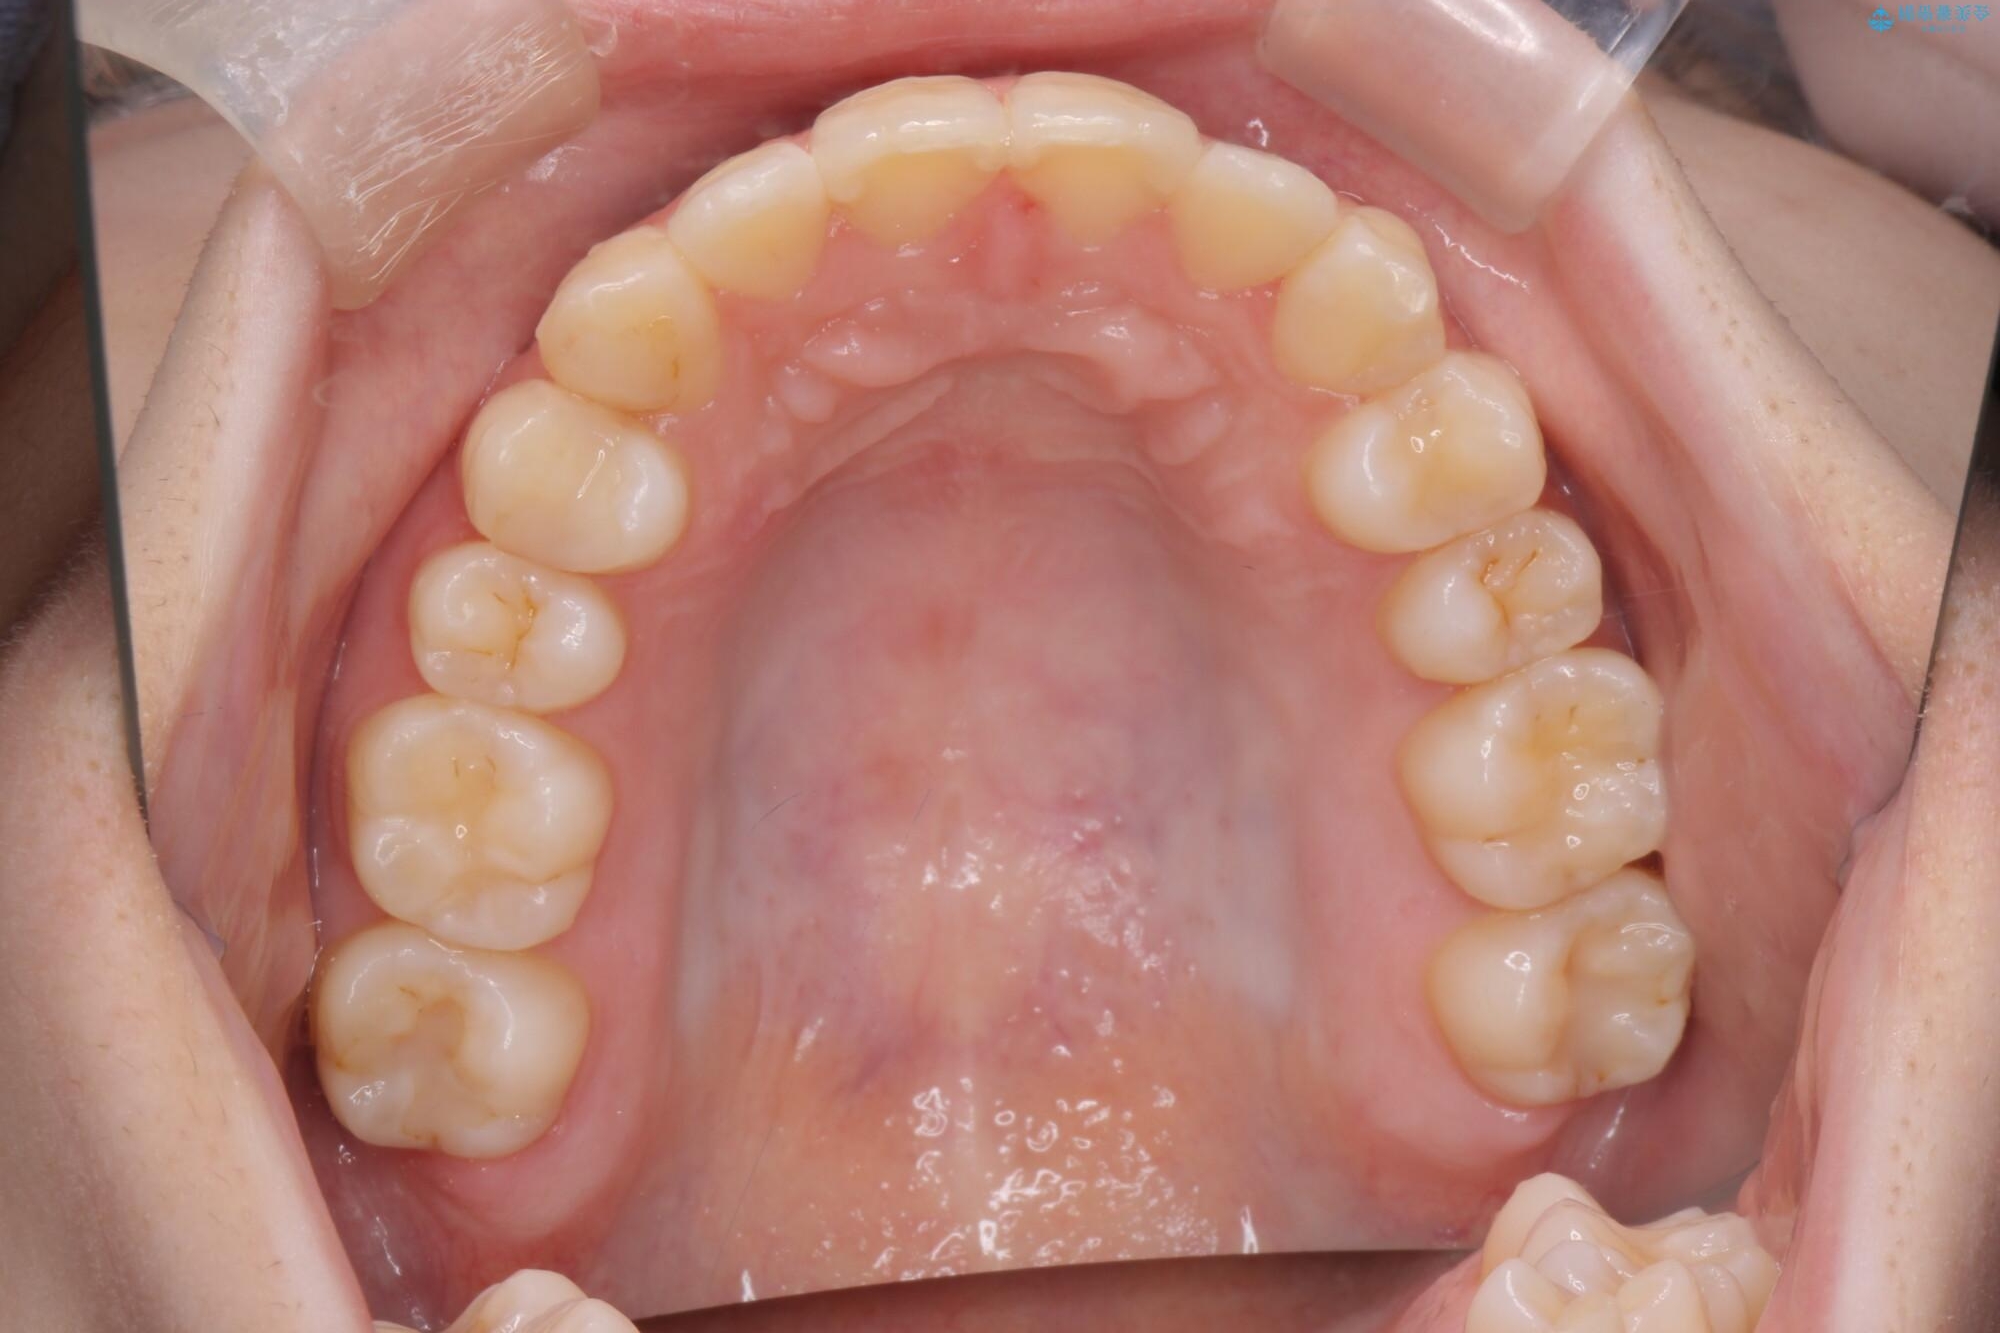

治療前

奥歯のガタつきをマウスピース矯正で改善 治療前画像 奥歯のガタつきをマウスピース矯正で改善 治療前画像 奥歯のガタつきをマウスピース矯正で改善 治療前画像